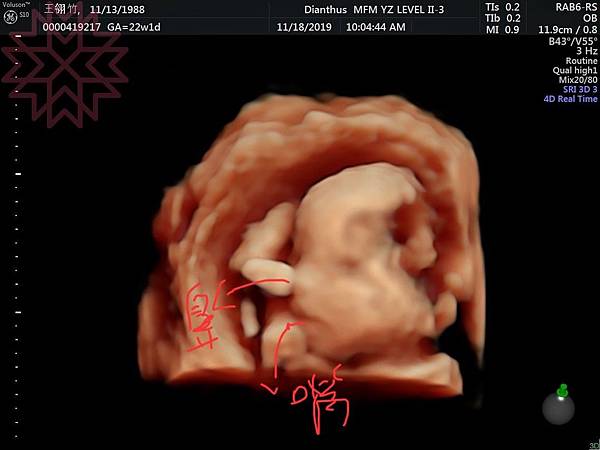

(桃子跟丸子的側面看起來好像XD)從第12周開始就是大家所說的穩定期